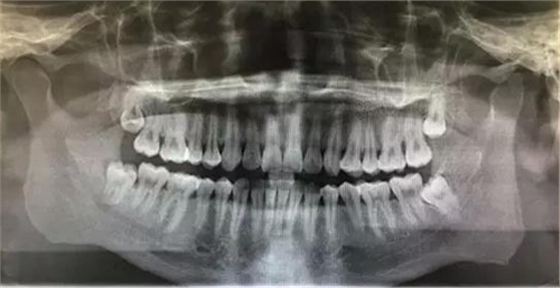

圖1.術(shù)前的全景片影像檢查:48合平面低于47合平面、高于47牙頸部